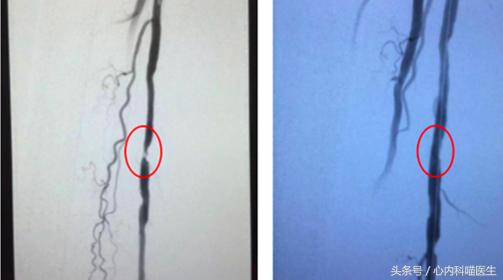

是由于下肢动脉粥样硬化斑块形成,引起下肢动脉狭窄、闭塞。表现为活动时下肢小腿出现疼痛,发凉等。

Diagram showing angioplasty for coronary artery